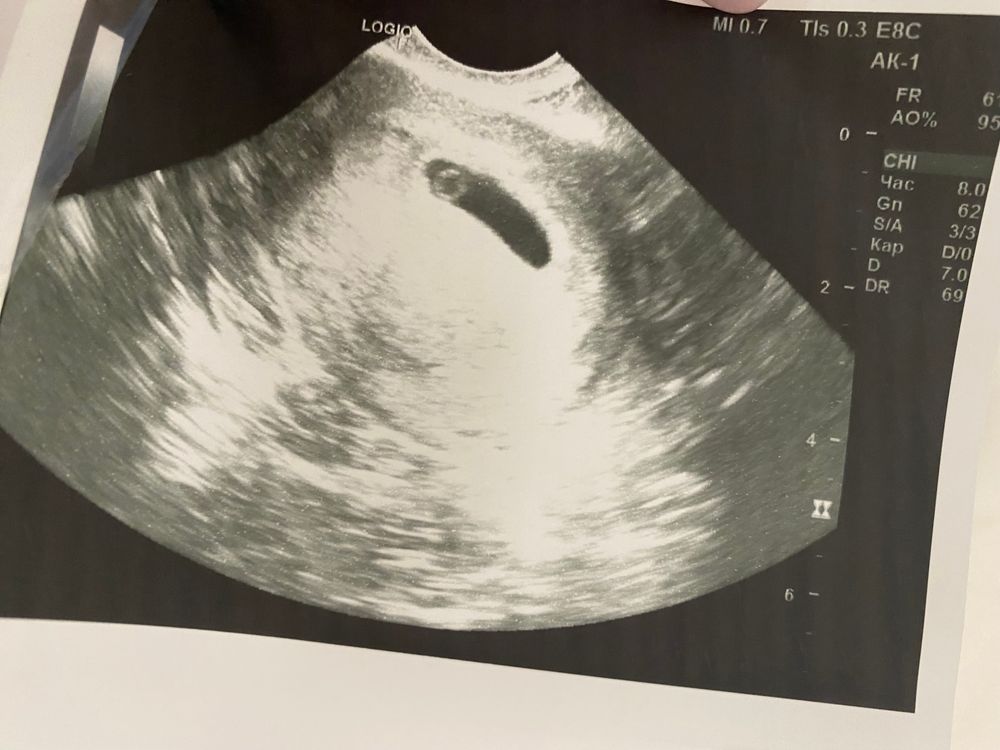

Дарья Кузнецова, мало ли что сказали. Тонус - это просто покакали и небольшой тонус получили. По сути ничего страшного в этом нет. Но так же стоит учесть, что аппарат УЗИ в принципе смотрит таким образом, что изображения вытянутые, отсюда и такие формы. Вот моя девочка, никакого тонуса не ставили: Изображение